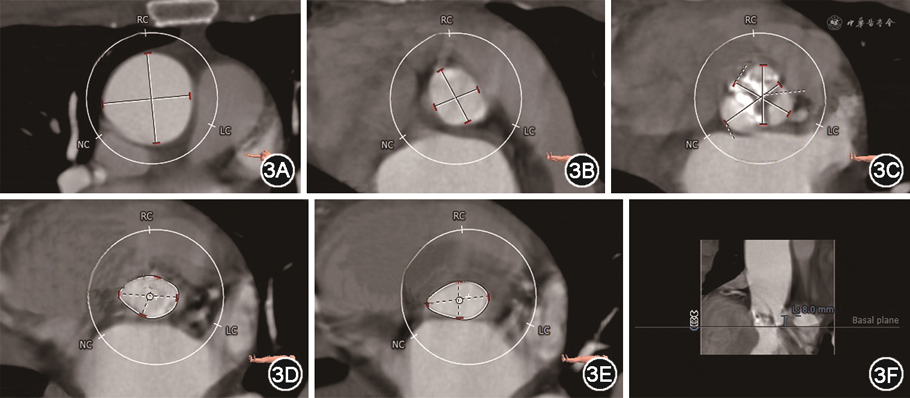

病例2 患者男,72岁,因“活动后气促半年,加重1个月”入院。否认高血压、糖尿病、冠心病史。入院体格检查:心率齐,主动脉瓣区可闻及收缩期喷射样杂音,二尖瓣区可闻及舒张期隆隆样杂音。超声心动图提示:风湿性心脏病,重度AS并轻度关闭不全(主动脉瓣口血流速度5.8 m/s,峰值压差138 mmHg,反流彩束面积3.0 cm2),中-重度MS并轻度关闭不全(二尖瓣后叶基底部回声增强,瓣环钙化,开放受限,二维超声心动图测得二尖瓣口面积1.3 cm2,反流彩束面积3.2 cm2,Wilkins评分为7)。诊断:重度AS,重度MS。患者年龄>65岁,NYHA心功能分级Ⅲ级,Euroscore Ⅱ评分4.1%,结合手术风险及患者意愿,决定行经导管瓣膜手术。术前CTA提示:主动脉瓣为二叶式type-1型,瓣叶游离缘重度钙化;左心室流出道内径18.1 mm,主动脉瓣环内径18.1 mm,窦部内径分别为22.5 mm(右冠窦)、23.7 mm(左冠窦)、25.3 mm(无冠窦),窦管结合部内径20 mm,升主动脉内径33.9 mm,左右冠状动脉开口高度分别为8.0、14.6 mm(图3)。考虑患者左冠状动脉开口位置低,主动脉根部较小,传统瓣架对瓣叶的径向推挤力量大,冠状动脉闭塞风险高,拟采用J-Valve心脏瓣膜置换系统(苏州杰成医疗)行经心尖TAVR,并同期行PBMV。J-Valve属于短支架瓣膜,且瓣膜通过定位翼固定,不依赖径向张力,对原生瓣膜的推挤力量不大,故阻塞冠状动脉开口的风险较小。